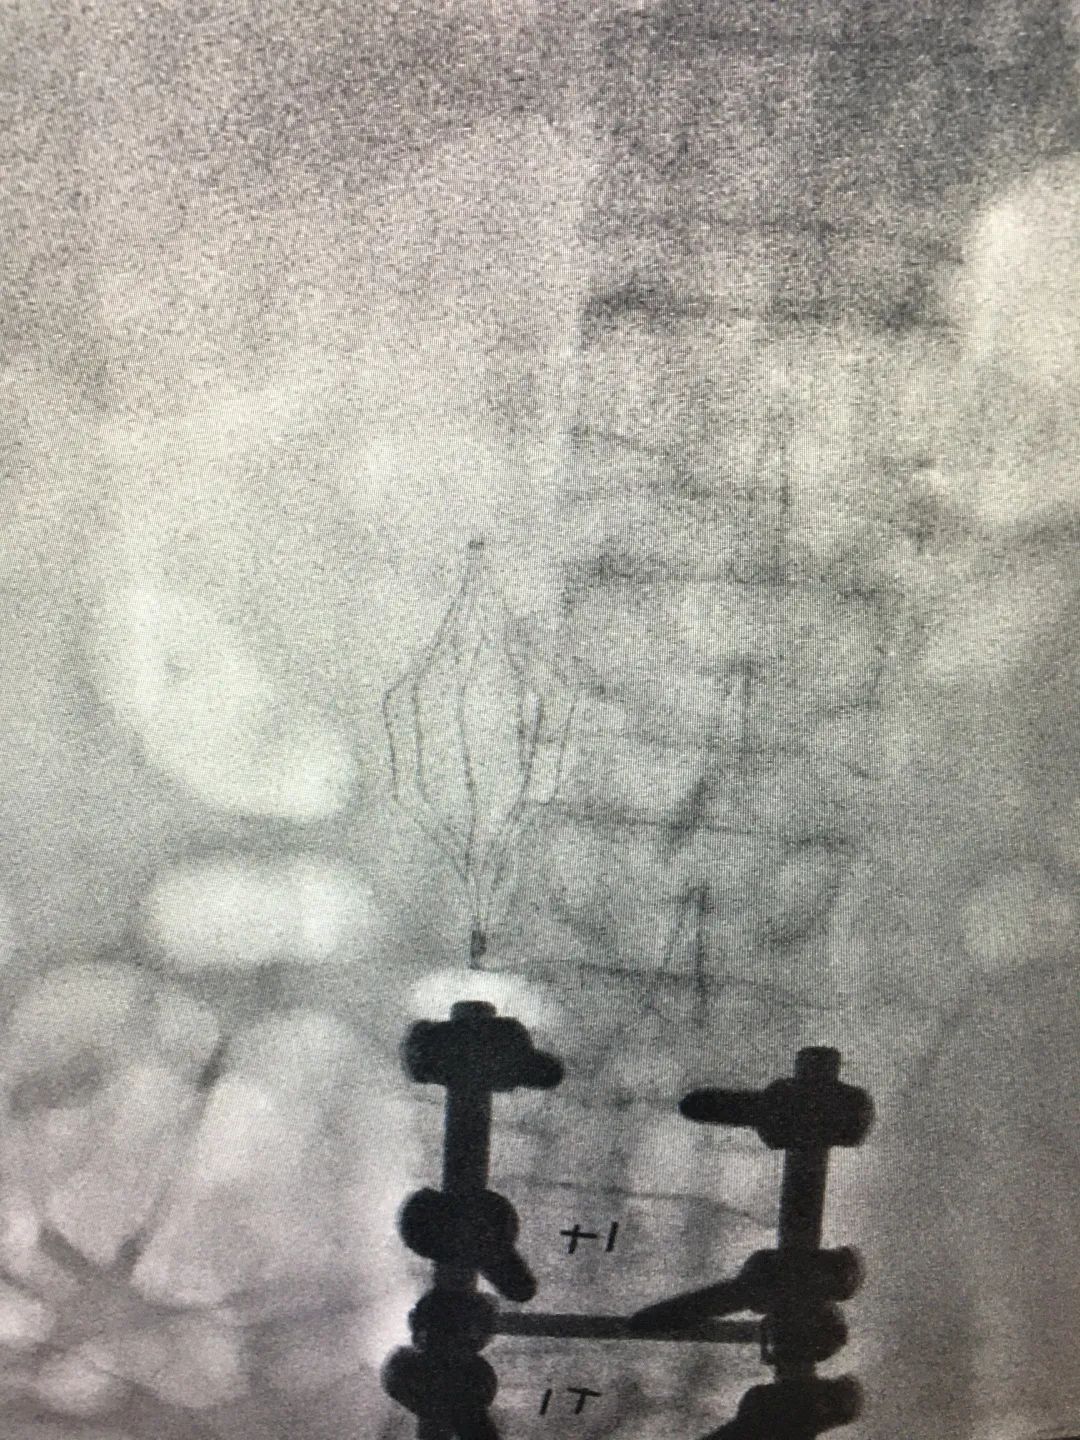

成功置入滤网

刘涛及其团队在介入室开展手术